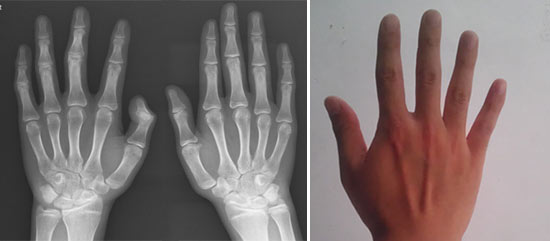

(图:林女士手部检查图显示,关节肿大明显,关节间隙狭窄)

双手X线检查:双手关节骨质疏松、关节间隙狭窄,有骨质增生情况,多处关节肿大明显。

(图:林女士来院复查时,检查结果显示双手掌指关节恢复正常)